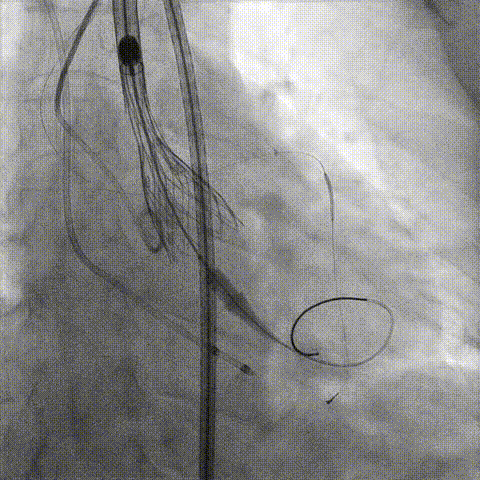

预置Telescope™导引延长导管及导丝保护左冠,

18mm球囊预扩张再次评估冠脉闭塞风险。

Telescope™+Runthrough

18mm*40mm 预扩张

预埋 Resolute Integrity 3.5*26mm

再次评估左冠开口

第一次释放

再次评估左冠开口,考虑调整瓣膜深度